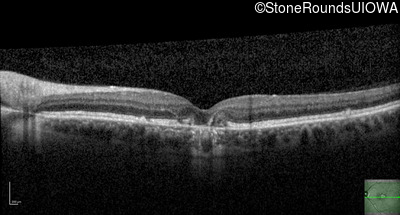

Optical Coherence Tomography - Right - 20/20

Exemplar / OCT Stack